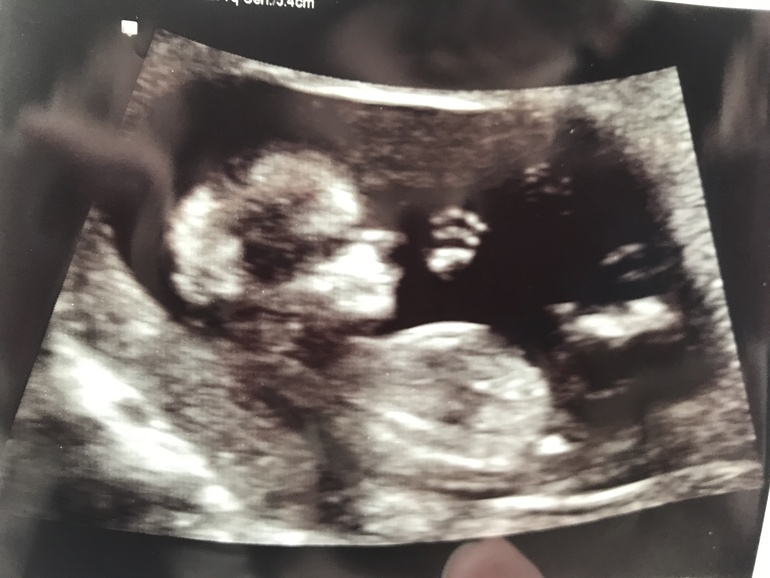

Наш малыш всем машет ручкой!

Девчат, только что со скрининга! Не могу не поделиться этим забавным кадром :) малыш дал пять :D

По м срок 12+4, по скрининг поставили 12+1. Все в норме. И это мое самое первое УЗИ за всю беременность, наконец-то впервые услышала сердце и вообще...это непередаваемо, смотреть как он там плавает, когда его тормошили ))) пальчик сосет. Такой малютка. Папа был с нами, говорит сидел там как обалдевший ))))

Я вообще перепутала сначала и удивилась что нос такой большой из-за того, что думала голова это только светлая часть :))) а там же ещё в тени часть головы, получается что нормальный нос :D но родня поржали, точно говорят, папин носяра уже ))))